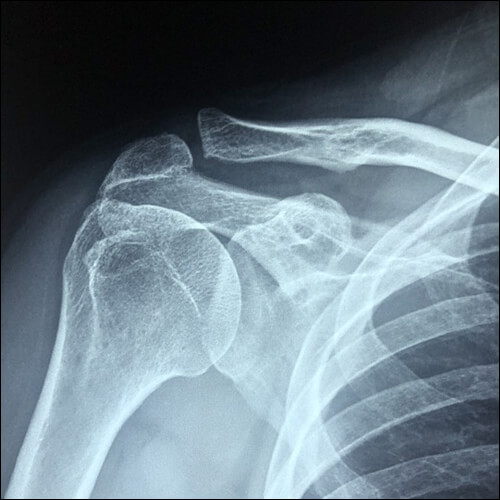

석회건염은 회전근의 노화로 인한 퇴형성 질환이라고 할 수 있습니다. 석회가 생겨서 힘줄 내부를 팽창시켜 통증을 유발하게 되므로 되도록 빠른 시간 내에 병원에 방문해서 치료를 받는 것이 좋습니다. X-레이나 초음파로 바로 확인할 수 있으며 주사요법, 체외 충격파 치료 등으로 치료합니다.